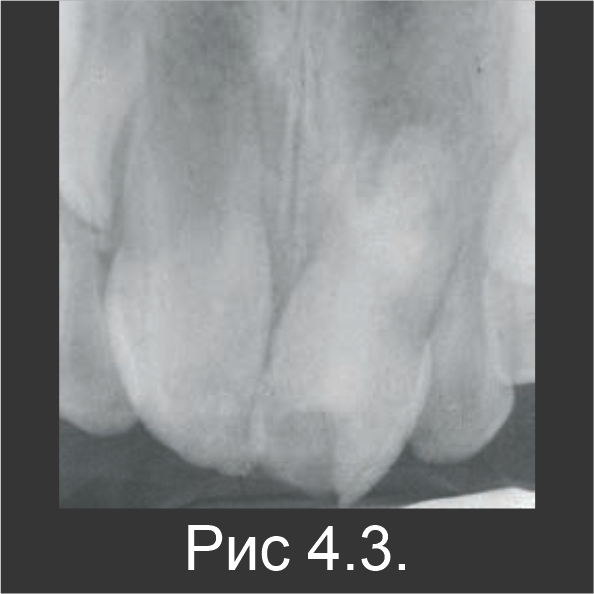

В ходе следующего посещения гидроксид кальция заменили материалом Biodentine™ (рис. 4.3). С помощью контрольного рентгенографического обследования, выполненного через 6 (рис. 4.4) и 18 месяцев (рис. 4.5), установили, что апексогенез зуба 21 продолжается и является сопоставимым с зубом 11, который не лечили (рис. 4.6).